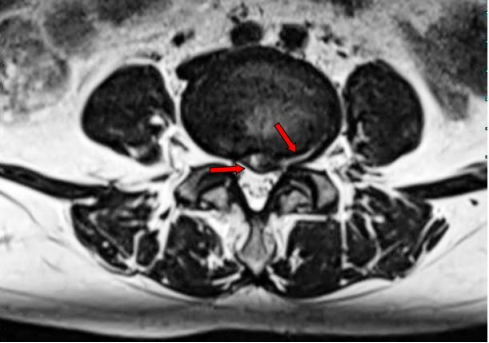

术前腰椎MR 可见腰4/5椎间盘中央偏左后突出,左后侧纤维环严重变薄,仅剩最外层纤维环完整。左侧侧隐窝狭窄,相应节段神经根受压。

术后3个月复查腰椎MRI,对比相同节段相同层面的图像,可见纤维环回缩明显,局部侧隐窝狭窄减轻,椎管狭窄减轻。